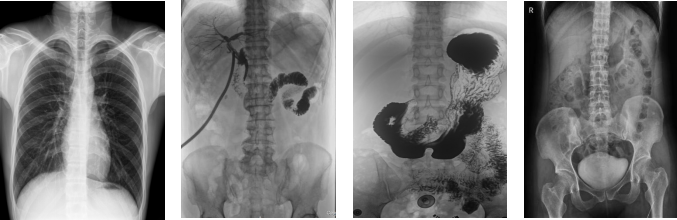

PLD8000C數(shù)字胃腸DR機全面突破傳統(tǒng)X射線攝影透視理念,成像部件采用新型動態(tài)平板探測器,輕松解決數(shù)字攝影、數(shù)字透視、數(shù)字造影等功能,并使數(shù)字透視獲得超大尺寸和清晰的圖像效果。滿足放射科、體檢中心、影像中心、內科、婦科、外科、急診科、骨科、創(chuàng)傷科、消化科等科室的各種臨床檢查需求。如果您想采購這款數(shù)字胃腸DR機,歡迎咨詢400-025-6366。